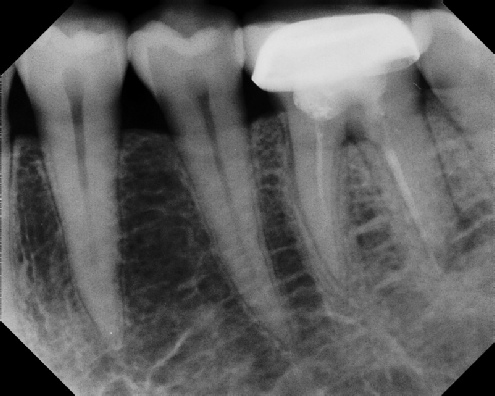

Root Canal Retreatment - Meriden 8 mos. recall Post-op Pre-op